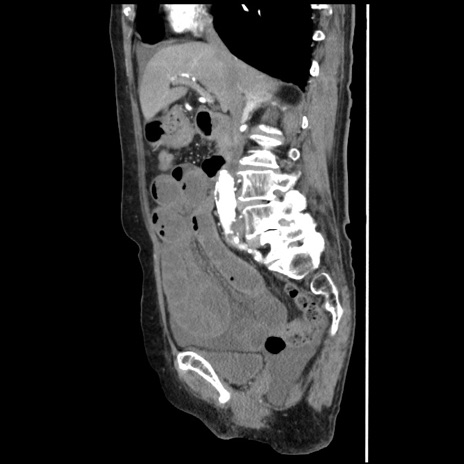

症例1(矢状断像)

【症例】80歳代女性

【主訴】腹痛

【現病歴】8時間前から腹痛あり来院。

【既往歴】糖尿病、脂質異常症、子宮体癌にて子宮全摘術

【身体所見】意識清明・会話良好だが腹痛で苦悶様、全腹部にわたって反跳痛と圧痛あり

【データ】WBC 13600、CRP 0.14、LDH 224、CK 90